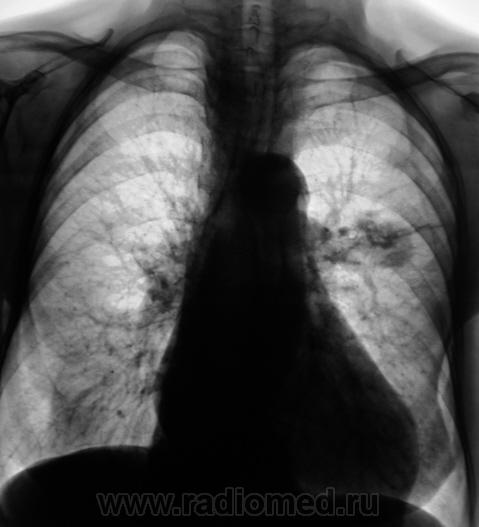

А клиника какова? ПО снимкам можно предположить и новообразование (как мне кажется наиболее вероятно) и туберкулому S6

Помоему образование, тяжистость ну очень интересная.

Неоднородность, очень плотное... гамартрохондрома, тератома, а-v-аневризма... Мне недостаточно для диагностики

Здравствуйте, уважаемый Валентин Львович! Склоняюсь к мысли периферического новообразования. На томограммах хорошо виден патогномоничный симптом "тень на веревочке". Ну и остальное. Неровные, нечеткие контуры, неоднородная структура. Зло!